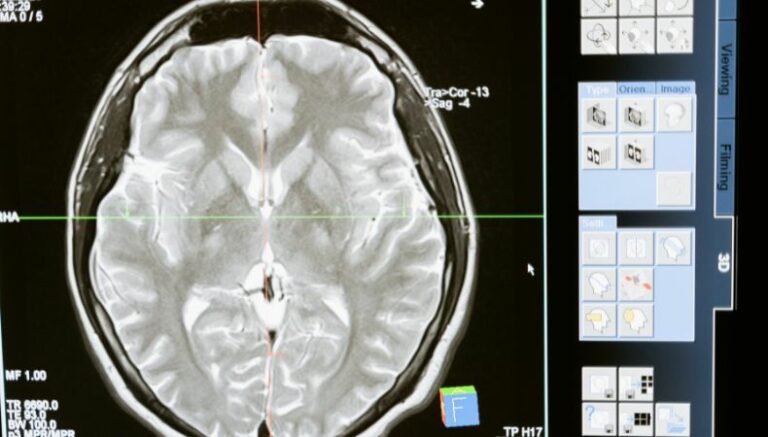

En el diagnóstico se realiza una evaluación médica por parte de un neurólogo, mediante los siguientes exámenes neurológicos:

- Imágenes por resonancia magnética (RMN).